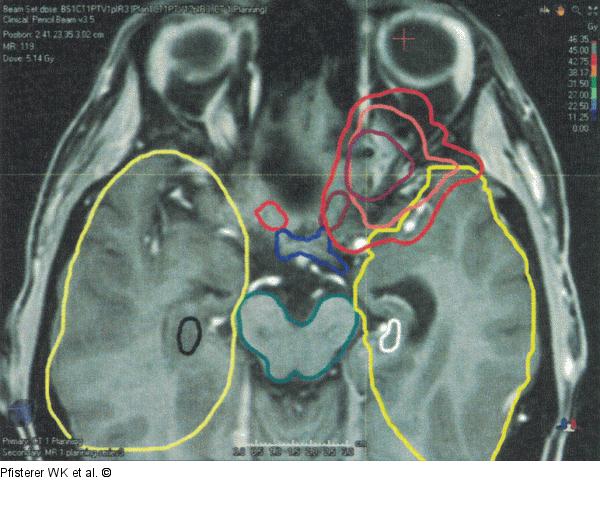

Abbildung 4: Risikoorgane Patientin 1: Risikoorgane Nn. optici (rot und rosa), Chiasma (blau), Hirnstamm (grün), Hippocampus (schwarz und weiß) und Temporallappen (gelb) |

Patientin 1: Risikoorgane Nn. optici (rot und rosa), Chiasma (blau), Hirnstamm (grün), Hippocampus (schwarz und weiß) und Temporallappen (gelb) |